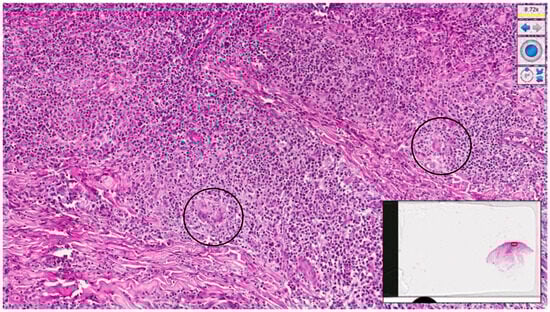

2. Case Presentation